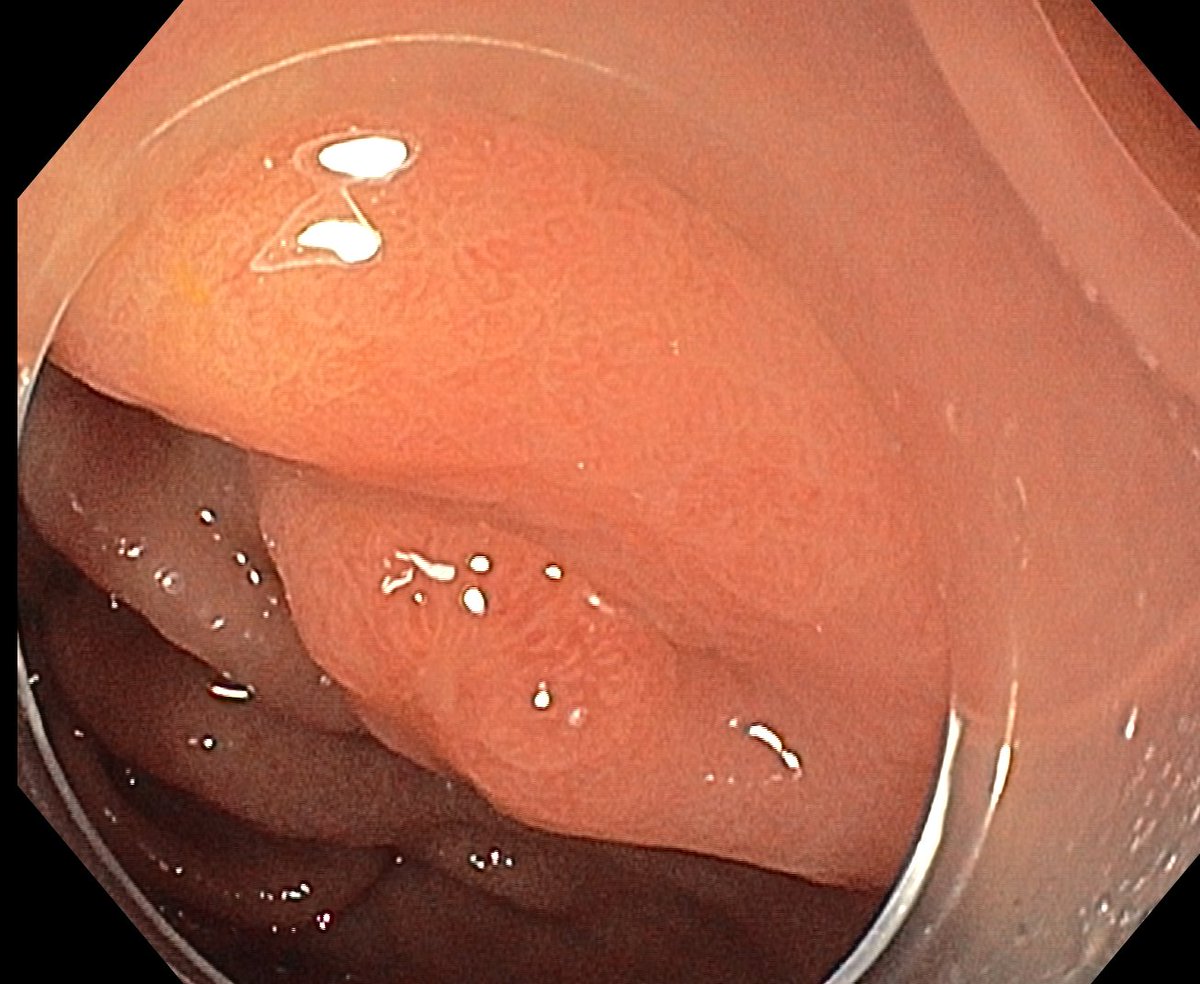

1. Antrum, low grade dysplasia. Removed via ESD. Specimen 43x32mm / dysplasia 20x13mm. R0